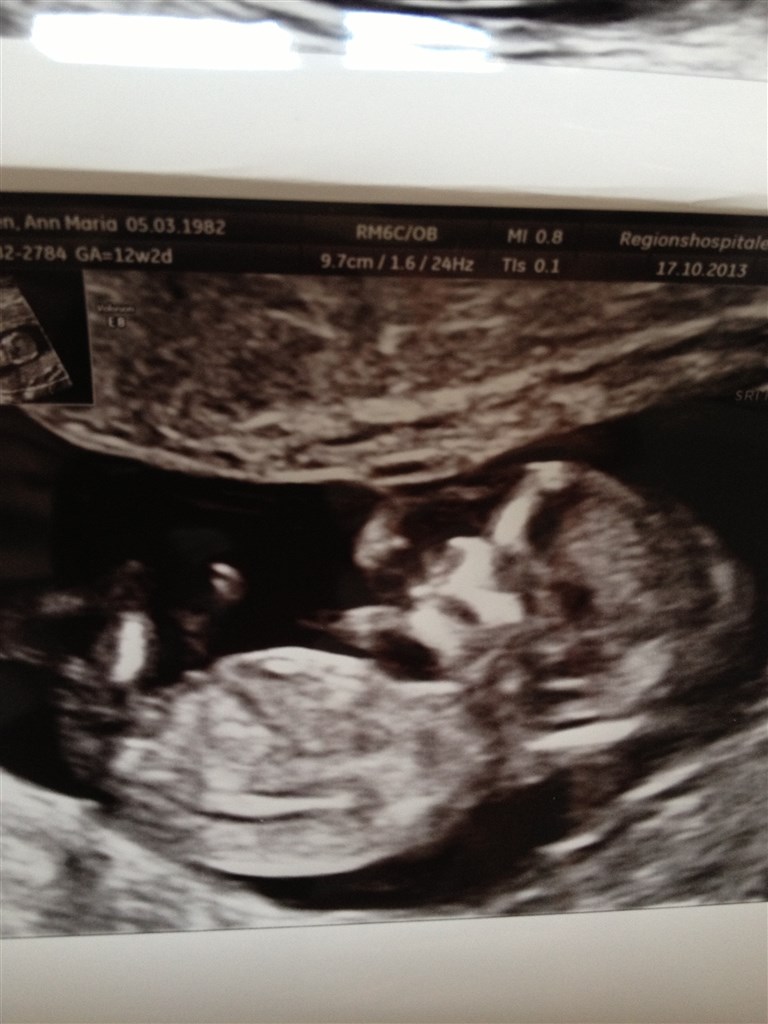

vi har i dag været til NF og jeg har simpelthen været sååå anspændt og nervøs, så da vi så en normal baby der havde er hjerte der slog, ja så var jeg opløst i lettelsen tårer.

De lavede en gennemskanning af baby og hjerne, hjerte, lunger, blære mv. var præcis som det skulle være, hjertet slog med 154 slag i minuttet og vi er i den lave risikogruppe. Vi hørte hjerte banke derudaf og så en baby der sprællede lystigt

Vedhæftede fotos (klik for at se i fuld størrelse)